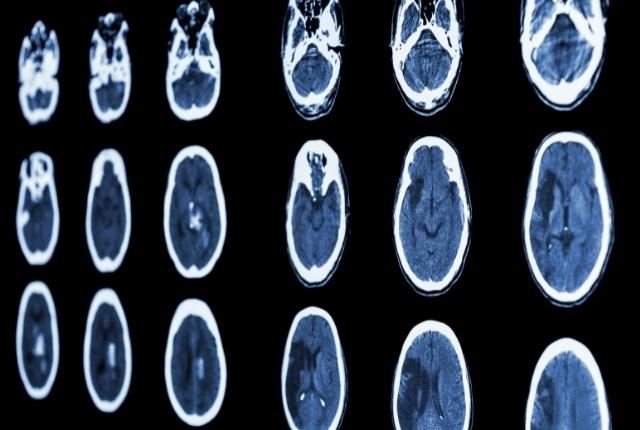

L'accident ischémique transitoire, de par sa nature transitoire, laisse en général peu de lésions identifiables par les médecins lorsqu’ils procèdent à un examen d’imagerie cérébrale. En cas de suspicion d’AIT, les équipes médicales procèdent à :

Un scanner cérébral (appelé aussi tomodensitométrie) ou une IRM (imagerie par résonance magnétique) pour visualiser d’éventuelles lésions et déterminer la cause primaire de l’AIT.